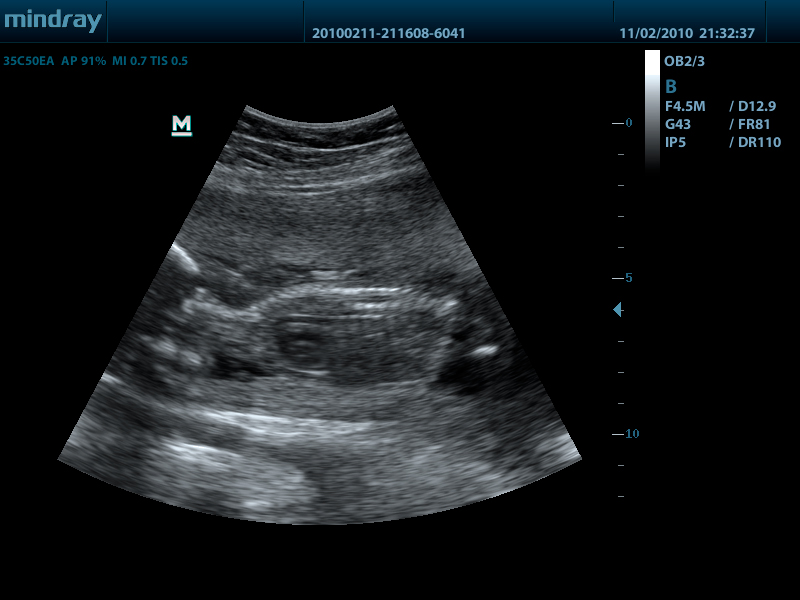

Mindray DP-50 – портативная цифровая ультразвуковая система с ЖК монитором 15 дюймов (1024Х768)

- iClear технология подавления помех и получения четких ультразвуковых изображений высокого разрешения

DP-50 – портативный УЗИ сканер разработан на базе новой платформы X-treme engine, используемой в хорошо зарекомендовавших себя цветных сканерах с доплером моделей DC-3, DC-7, DC-6. Эта платформа открывает возможности для расширений до уровня цветных сканеров и совместимости с широким диапазоном периферийного оборудования. X-treme означает интеллект, высокую скорость обработки данных, многоуровневую передачу сигналов, а также возможность оптимизации изображения и модульного расширения.

Качество изображения:

- iBeam: функция улучшения разрешающей способности изображения

- iClear: функция подавления шумов на изображении для улучшения детализации и контрастности изображения

Конвексный датчик 35C50EA (2.0/3.5/4.5/5.0/Н5.0/Н6.0) R50